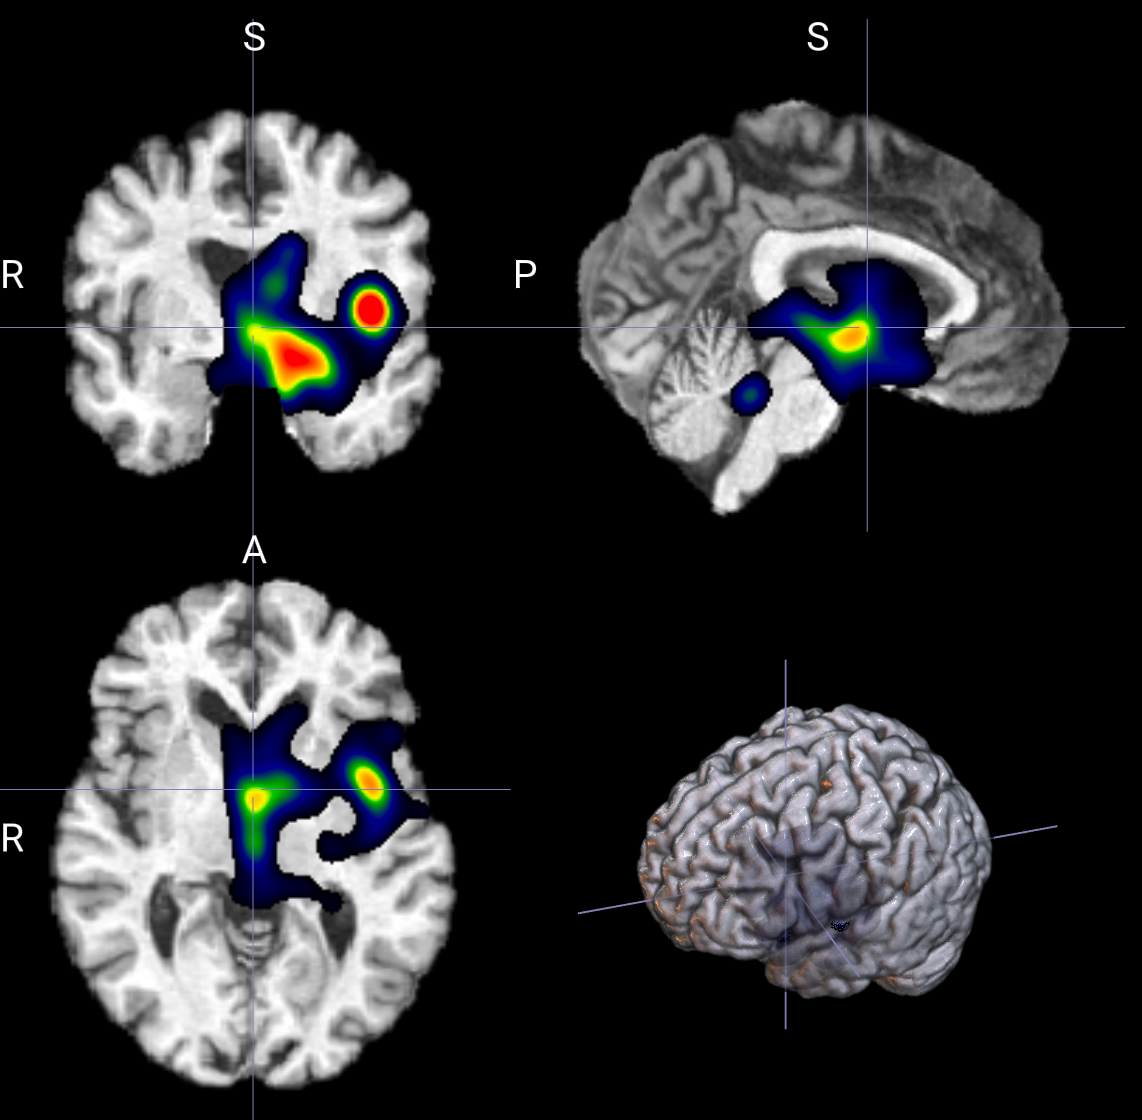

输出示例